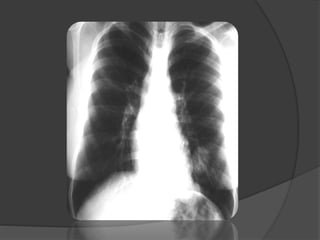

Imagerie

 La radiographie du thorax: Diagnostic (+)

Topographie

 Hyper clarté homogène compressive

 Trame vasculaire conservée mais grêle

 Signes de distension thoracique

 Hernie médiastinale + refoulement

controlatéral

 Pseudo-pneumothorax